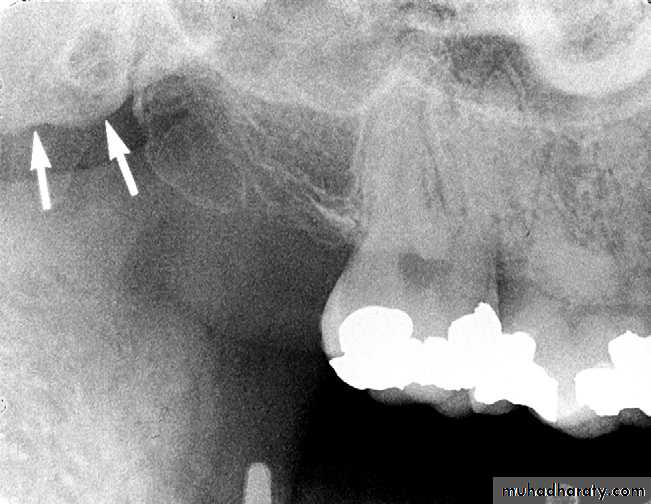

CORONOID PROCESS:

The coronoid process is a marked prominence of bone on the anterior ramus of mandible. Radiographically the coronoid process is not seen on mandibular periapical radiography but dose appears on maxillary periapical film as triangular radiopacity superimposed over the maxillary tuberosity region.